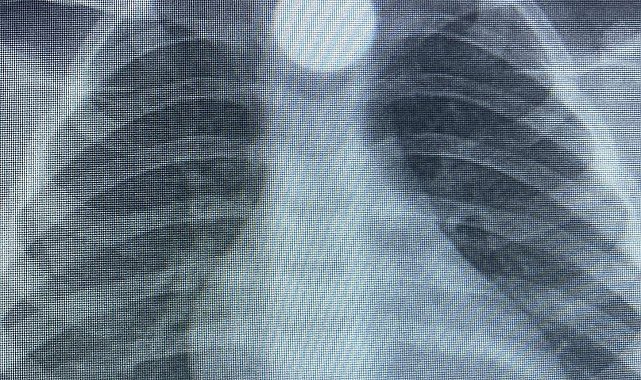

BURSA'nın İnegöl ilçesinde evde bulup yuttuğu 50 kuruş madeni para yemek borusunda takılı kalan Bilal K. (3), hastanede tedaviye alındı.Olay, kırsal Yeniceköy Mahallesi'nde meydana geldi. Bilal K., evde oynarken yerde bulduğu 50 kuruş madeni parayı ağzına alıp yuttu. Durumu fark eden ailesi, Bilal K.'yi özel araçla İnegöl Devlet Hastanesi'ne götürdü. Hastanede yapılan kontrollerde, madeni paranın Bilal K.'nin yemek borusunda takılı kaldığı belirlendi. Burada ilk müdahalesi yapılan Bilal K., daha sonra ambulansla Bursa Yüksek İhtisas Eğitim ve Araştırma Hastanesi'ne sevk edildi. Bilal K.'nin tedavisinin sürdüğü öğrenilirken, olaya ilişkin soruşturma başlatıldı.